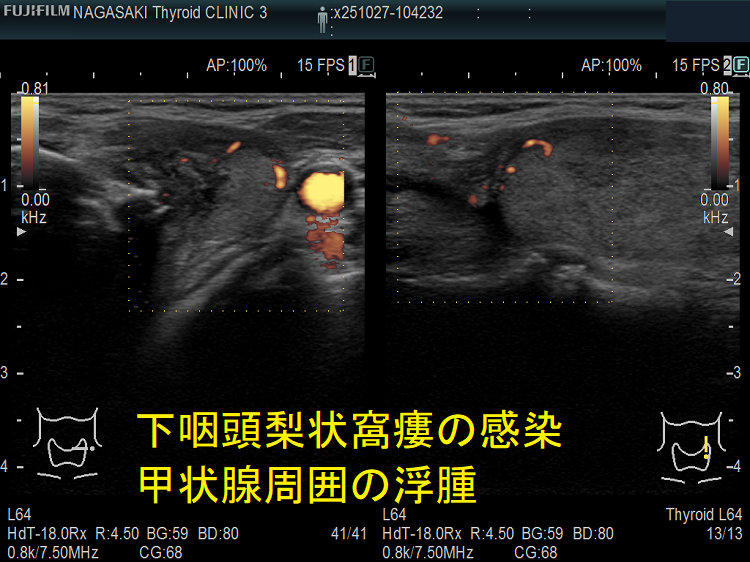

- 超音波検査(エコー検査)で、甲状腺内~甲状腺外の周辺組織に続く境界不明瞭な低エコー領域を認めます。

甲状腺外の低エコー領域があれば、診断は容易ですが、初期は甲状腺内に限局した低エコー領域なので亜急性甲状腺炎との鑑別が難しい。筆者の経験では、どちらの低エコー領域も内部不均一になりますが、亜急性甲状腺炎の低エコー領域は境界不明瞭で飛び石状ですが、急性化膿性甲状腺炎の低エコー領域は単発性・連続性で、比較的境界不明瞭が多い。

その他、急性化膿性甲状腺炎では、

①甲状腺内の低エコー領域は片側性が多い(特に下咽頭梨状窩瘻は左側)。甲状腺悪性リンパ腫のような入道雲様の事も。

②甲状腺外の低エコー領域は滲出液・膿瘍で、頭内側に多い

③腫瘍内感染では、腫瘍内に低エコー領域、腫瘍の周囲に不均一な低エコー領域

急性化膿性甲状腺炎に至らない下咽頭梨状窩瘻の感染もあります。下咽頭梨状窩瘻が甲状腺内でなく、甲状腺周囲に開口している場合に起こります。